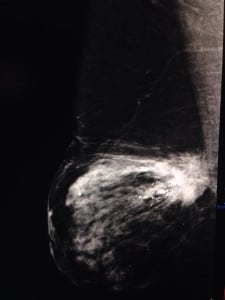

Caso 1.

((Mastografía digital: vemos en el tercio posterior un nódulo denso de márgenes espiculados, asociado a calcificaciones que varían en forma y densidad: relación a un cáncer ductal invasor))